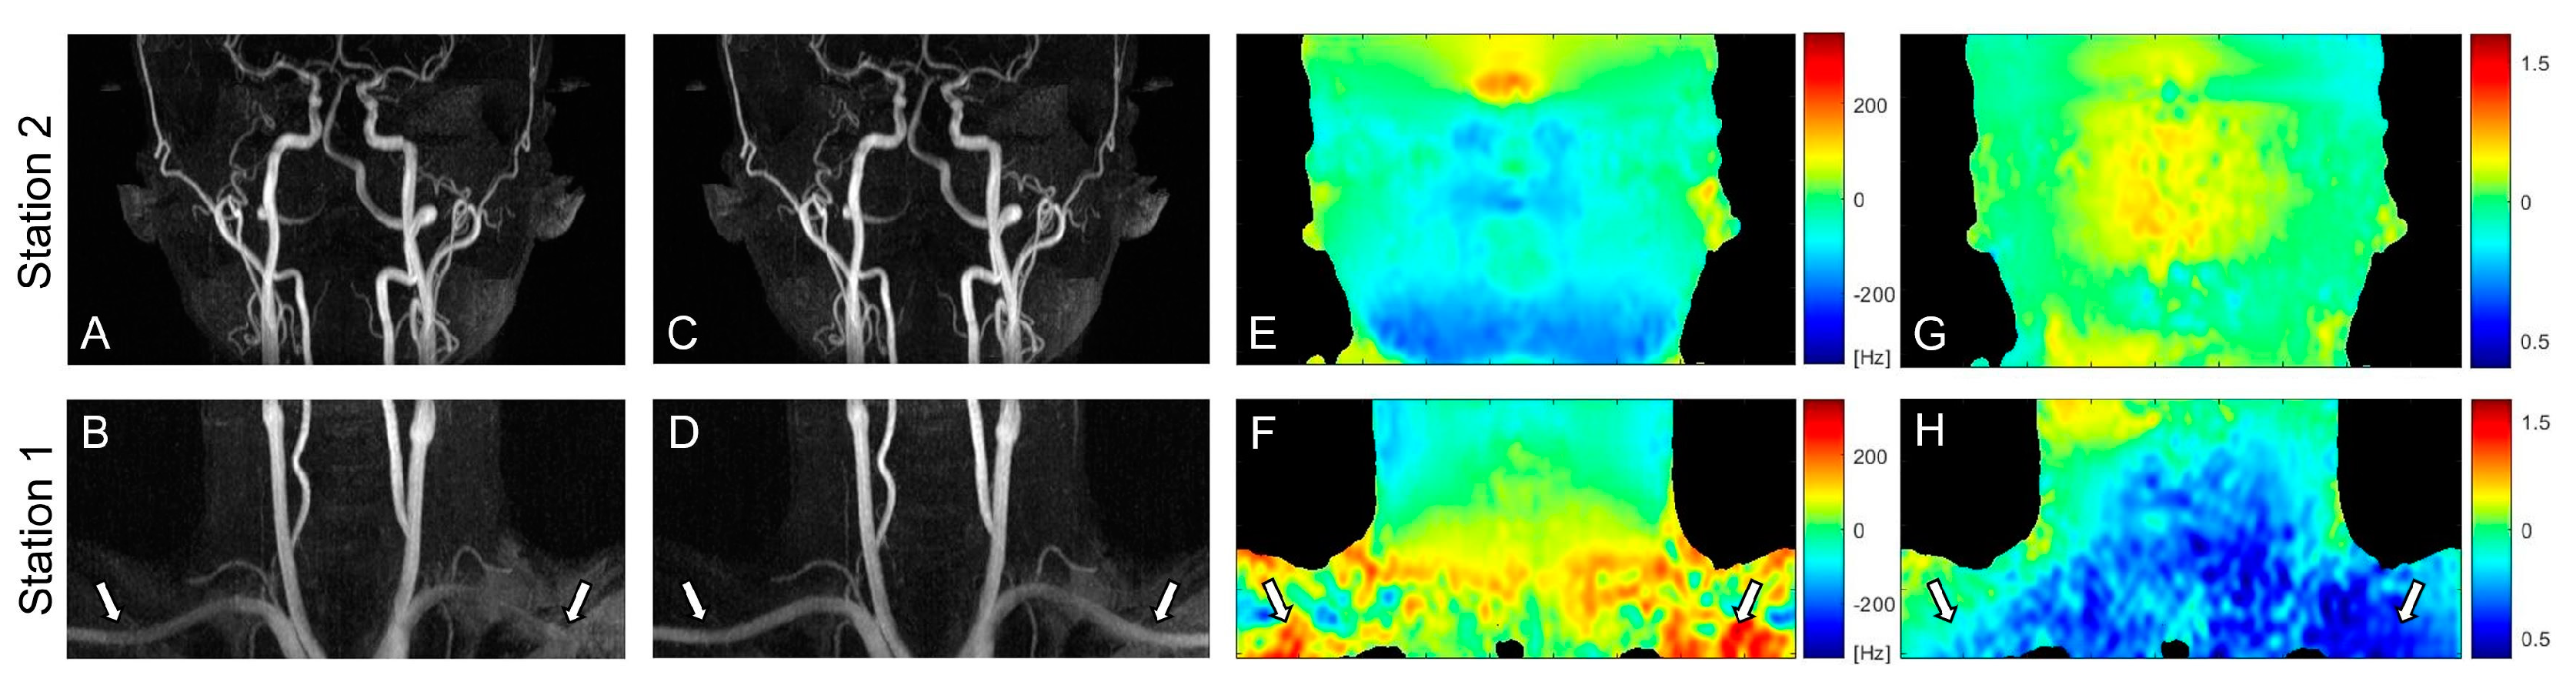

Figure 3 contains partial coronal maximum intensity projection (MIP) images of the whole-neck VS-MRA obtained with the original (A, B) or field-error-compensated VS preparation pulses (C, D). B0 and B1 field maps are also shown in the same subject (E-H). The original VS preparation resulted in signal loss in the subclavian arteries, which involve large magnitudes of B0 and B1 field errors (arrows). Using the pre-compensated VS preparation, this signal loss was reduced, while the high signal strength was maintained in other arterial branches. Little difference was observed between the images from the two VS preparations in station 2, presumably due to relatively small field offsets (A, C).

Figure 3.

Coronal maximum intensity projections (MIPs) of VS-MRA images obtained using VS preparations without (A,B) and with pre-compensation (C,D), along with off-resonance maps (E,F) and B1 maps (G,H). The original VS preparation suffers from arterial signal loss in the regions of large off-resonance and low B1 field, whereas the pre-compensated VS preparation significantly improves the arterial visualization in the same regions (arrows). The images in station 2 (A,C) show little difference due to relatively low field offsets (E,G).